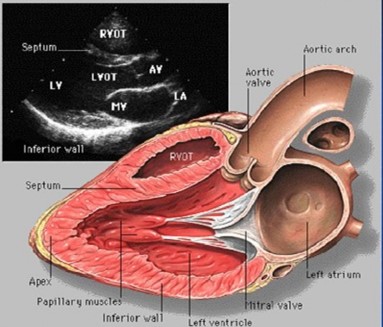

14:50,在得知患者经静脉给予维生素K1,2小时前(13:00)INR已降到2.73时,我们决定再次复查凝血指标后确定用药。同时,在没有经食道超声的条件下,由我们团队中来自空军总医院的马斌博士为患者做心脏超声,了解心功能状况并看看有没有明显的血栓,结果良好。